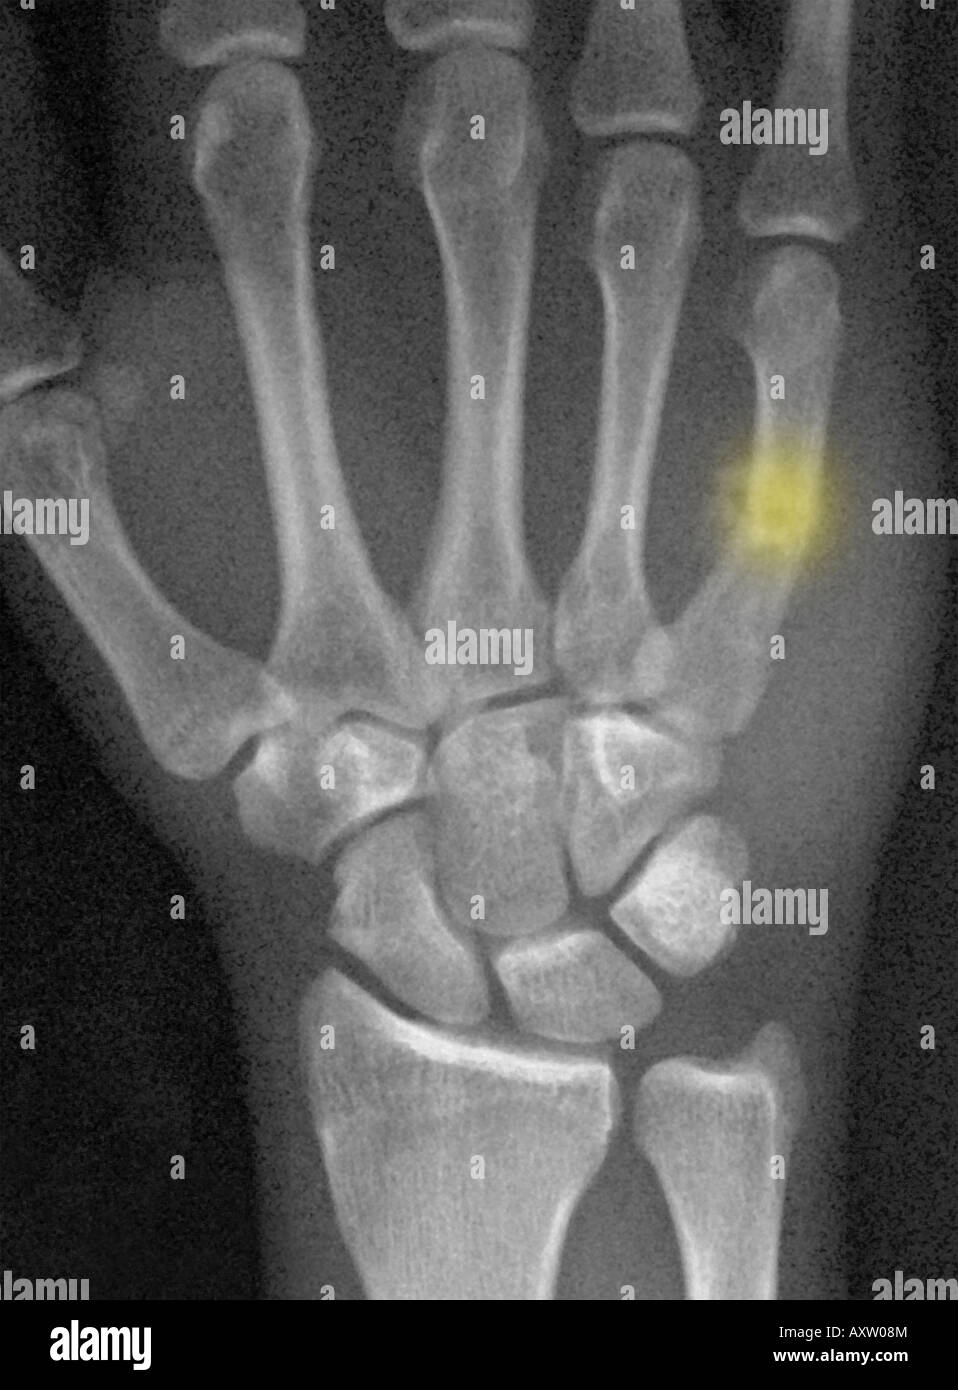

Boxer's Fracture X Ray . Contributed by s bhimji md Fracture of the 4th or 5th metacarpal caused by an axial load, typically from punching a person or object; Boxer’s fracture is the fifth metacarpal neck fracture resulting from direct trauma to the clenched fist. Typical case of boxer's fracture, as a transverse fracture of 5th metacarpal neck. Boxer’s fractures are fractures of the ring or small metacarpal neck that typically occur following an axial impact with a clenched. Pain or swelling along the 4th or 5th metacarpals;. Emergency management of boxer’s fractures.

Boxer fracture. Radiograph shows a fracture of the fifth metacarpal Boxer's Fracture X Ray Pain or swelling along the 4th or 5th metacarpals;. Boxer’s fractures are fractures of the ring or small metacarpal neck that typically occur following an axial impact with a clenched. Contributed by s bhimji md Fracture of the 4th or 5th metacarpal caused by an axial load, typically from punching a person or object; Boxer’s fracture is the fifth metacarpal. Boxer's Fracture X Ray.

hand xray of a 57 year old man showing a 5th metacarpal (boxer's Boxer's Fracture X Ray Emergency management of boxer’s fractures. Boxer’s fractures are fractures of the ring or small metacarpal neck that typically occur following an axial impact with a clenched. Contributed by s bhimji md Typical case of boxer's fracture, as a transverse fracture of 5th metacarpal neck. Pain or swelling along the 4th or 5th metacarpals;. Boxer’s fracture is the fifth metacarpal neck. Boxer's Fracture X Ray.

xray of the hand of a man showing a healing boxer's fracture, a break Boxer's Fracture X Ray Emergency management of boxer’s fractures. Boxer’s fractures are fractures of the ring or small metacarpal neck that typically occur following an axial impact with a clenched. Boxer’s fracture is the fifth metacarpal neck fracture resulting from direct trauma to the clenched fist. Fracture of the 4th or 5th metacarpal caused by an axial load, typically from punching a person or. Boxer's Fracture X Ray.